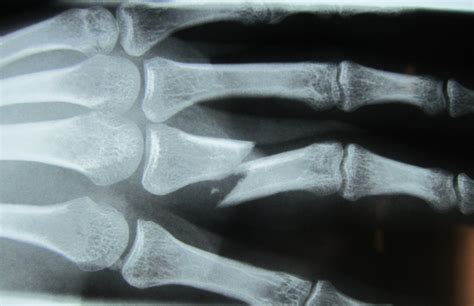

Diagnosing a broken finger typically involves a physical examination and imaging tests. During the physical exam, the doctor will assess the finger's range of motion, swelling, and any deformities. Imaging tests, such as X-rays, are often used to confirm the diagnosis and determine the extent of the fracture.

Hand with broken finger